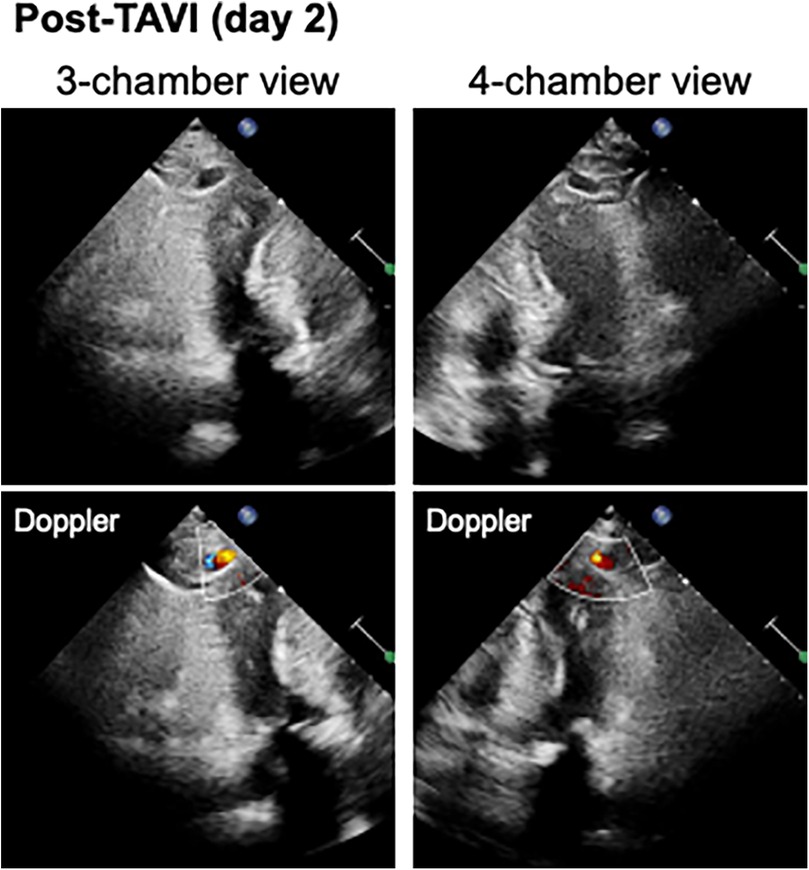

A blood test obtained one day after TAVI revealed marked elevation of myocardial enzymes: creatine kinase (CK) at 1921 U/L and CK-MB at 236 U/L. Despite these findings, the patient did not report chest pain, and electrocardiography showed no ischemic changes such as ST-segment elevation or new Q waves. Given the absence of clinical and electrocardiographic evidence of acute myocardial infarction, alternative causes of enzyme elevation were considered. These included myocardial injury secondary to mechanical stress from the procedure itself, microvascular embolization, temporary guidewire-induced trauma, or global ischemia due to rapid pacing during valve deployment. Initial transthoracic echocardiography revealed no regional wall motion abnormalities. However, a repeat study performed three hours later identified new, localized hypokinesis at the left ventricular apex, although the volume of pericardial effusion remained unchanged. To further investigate, contrast-enhanced CT was performed five hours after the enzyme elevation was noted. This allowed us to confirm the presence of a pseudoaneurysm at the left ventricular apex. And, by color doppler echocardiography, we also confirmed abnormal flow within the newly visualized apical structure, consistent with a pseudoaneurysm that was seen in the CT scanning (Figure 3). Due to the findings of rapidly expanding of the pseudoaneurysm, and the extremely high potential risk of cardiac rupture, emergency surgical intervention was undertaken. Intraoperatively, a pseudoaneurysm measuring approximately 7 mm was identified on the lateral aspect of the left ventricular apex. The surrounding myocardial tissue was noted to be fragile, suggesting localized necrosis or structural compromise. Surgical repair was performed using two bovine pericardial patches (4 × 1 cm), which were sutured in place with continuous stitching. Postoperatively, the pseudoaneurysm cavity was largely thrombosed, and follow-up CT imaging demonstrated a reduction in the contrast-enhancing area to approximately 5 mm (Figure 4). One month later, repeat CT imaging showed no residual aneurysmal structure. She was transferred from the intensive care unit on postoperative day 9 and discharged from the hospital on day 27. She continues to do well on outpatient follow-up.

Figure 3. The color doppler echocardiography visualized a cavity and abnormal blood flow inflow within the apical structures consistent with a pseudoaneurysm.